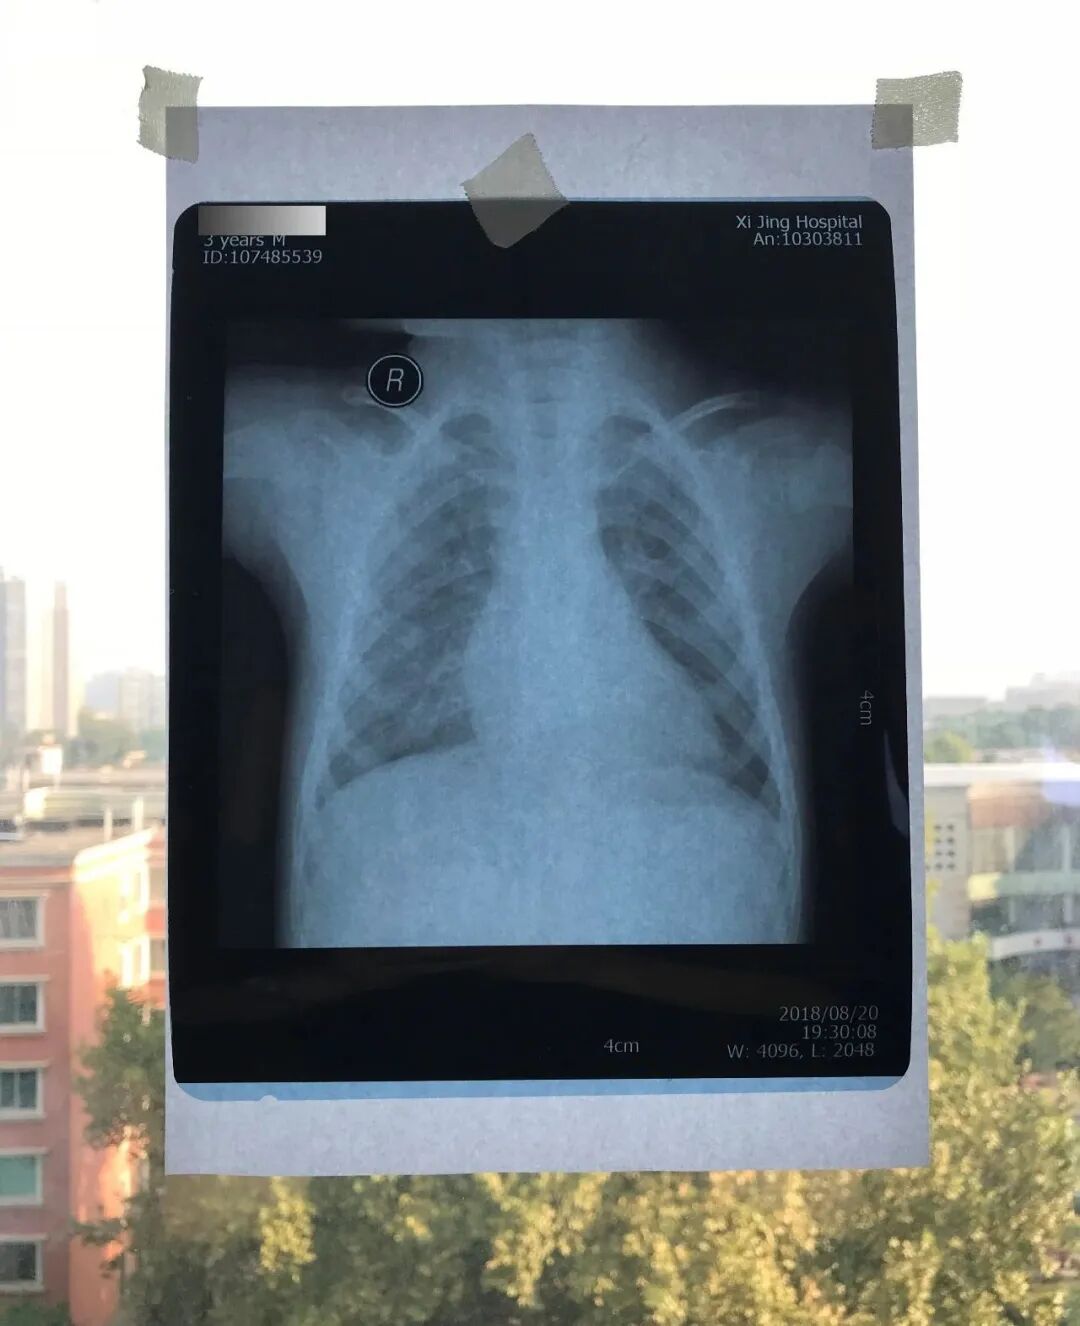

翻拍打印胶片是有讲究的,不能随意拍,要知道主治医生在诊室观片,都要在观片灯下看上好一会,所以翻拍出来的胶片,一定要自己先看下拍的是否清楚。更不能拍的倾斜、反光,透出背景,这样会影响看片,结果要不就是误诊,要不就是没法看。

正确的拍摄方法可以参见:刀客居的原创丨医生及患者通用:如何用手机翻拍X线片,磁共振片子,CT片子进行网络求医、病例讨论及保留资料,其讲述的拍摄步骤主要如下:

拍摄设备:像素较高的手机,或者数码相机,现在质量好一些的手机就可以的,切记:关闭闪光灯!

拍摄者着深色衣服,以防浅色衣服在片子上反光成像。

白天拍摄,窗户外光亮,室内关灯。

如果能在医院找到医生专用的观片灯,则最为最佳选择。

如果没有观片灯,准备一张白纸(白纸大小最好大于等于,被拍摄的片子大小,当然可以拼接)。

如果家里有电脑(台式机或笔记本电脑均可),也可以使用电脑显示器调白色后进行拍摄。使用电脑拍摄的时候,在电脑打开幻灯软件Powerpoint (PPT),新建一个空白文档,纯白色的,然后把该文档全屏播放模式下,即可实现全屏白色。

02

将准备好的白纸贴于窗户玻璃上,然后将X光片或磁共振或CT片子贴于白纸上。如果用的是电脑显示器翻拍片子,按照第1条将显示屏变白色后,将片子贴于显示器上进行拍照。拍照时一定要正对着片子拍,注意横平竖直,拍端正了,不要拍歪斜了。